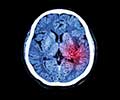

What is Brain Hemorrhage?

Brain hemorrhage otherwise called intracranial hemorrhage (ICH) is a type of hemorrhagic stroke that is specified by bleeding inside the skull and/or brain. It is a life-threatening emergency where the bursting of arteries causes brain damage that may even extend into the surrounding brain structures like meninges (protective brain layers) and ventricles (brain cavities)(1✔ ✔Trusted Source

- CT scan: The gold standard tool of investigation for a brain hemorrhage is a CT scan. It helps in determining the site of the bleed along with its extent.